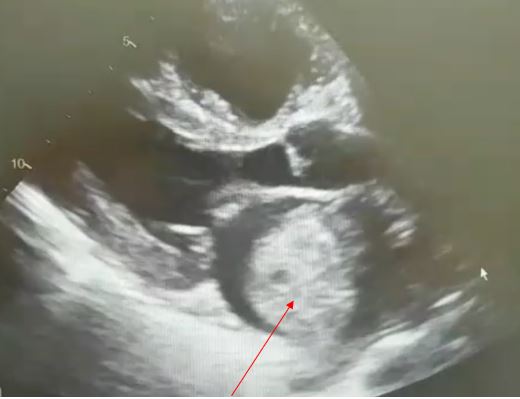

En la actualidad, los tumores cardiacos se diagnostican mediante los estudios de ecocardiografía (transtorácica y transesofágica) y la resonancia magnética cardiaca.

Los mixomas son los tumores cardiacos benignos más frecuentes, aparecen sobre todo en el sexo femenino y se suelen diagnosticar entre la tercera y sexta década de la vida. Suelen localizarse, en el lado izquierdo del corazón, suelen ser masas intracavitarias únicas, de tacto gelatinoso y friable, muy móviles, ancladas mediante un pedículo al septo interauricular, y pueden alcanzar un tamaño de hasta 5-6 cm.

Imagen de tumor por ecocardiografía